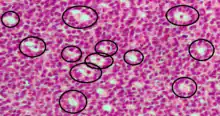

Call–Exner bodies

Call–Exner bodies, giving a follicle-like appearance, are small eosinophilic fluid-filled punched out spaces between granulosa cells.[1] The granulosa cells are usually arranged haphazardly around the space.

They are pathognomonic for granulosa cell tumors.

They are composed of membrane-packaged secretion of granulosa cells and have relations to the formation of liquor folliculi which are seen among closely arranged granulosa cells.